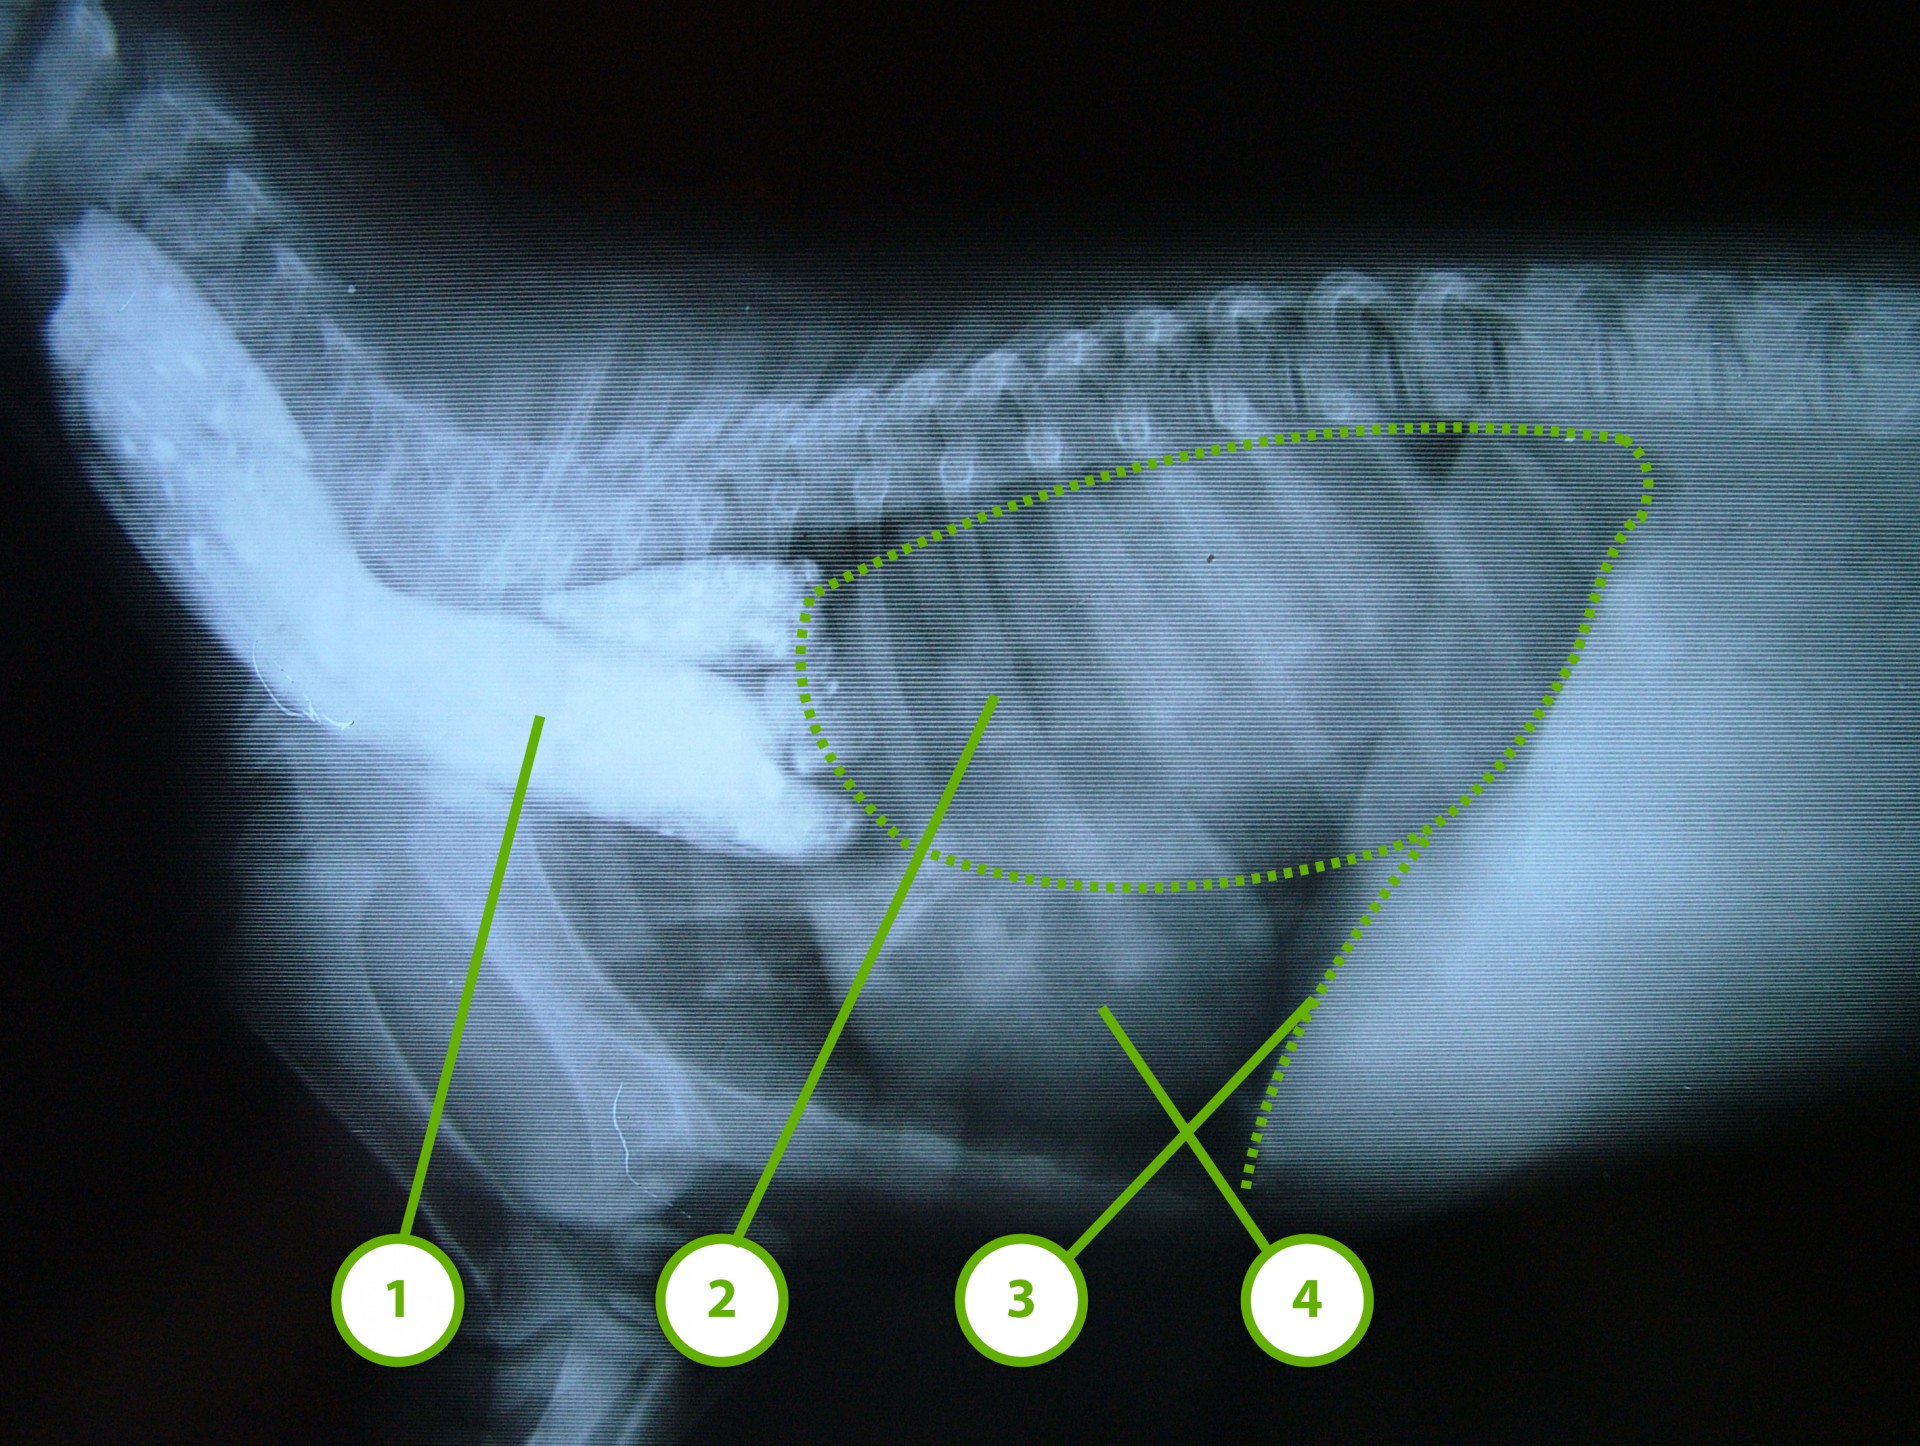

• A másik esetben a nyelőcső rekeszen át történő haladása körül a rekesz rétegeiből csak a savóshártya kettőzet található meg, aminek a következtében ezen a területen a rekesz határoló funkciója gyengül, a hasüregi szervek(elsősorban a gyomor) a nyelőcső rekeszizomban található részén keresztül a mellüregbe türemkedik (hiatus hernia ).

Mindhárom rekeszsérv forma meglehetősen ritkán fordul elő. A diagnózis felállítása a kórelőzmény, a klinikai tünetek a mellkas röntgenvizsgálata, a hasüreg ultrahangos vizsgálata alapján lehetséges.A rekeszsérv műtéti ellátása során a legnagyobb kihívást az jelenti, hogy a hasüreg megnyitását követően a sérvkapun keresztül levegő kerül a mellüregbe, ezáltal az állat spontán légzése leáll, így a műtét teljes ideje alatt asszisztált lélegeztetésre van szüksége.A műtét során a mellkasba előesett szerveket reponáljuk, a rekesz folytonosság hiányát megszüntetjük és a mellkasban lévő szabad levegőt eltávolítjuk, ezzel biztosítva az állat spontán légzését. A műtétet követő napokban legfontosabb feladat a vérkeringés és a légzés folyamatos, kórházi körülmények közötti kontrolálása.Az idejében felismert és megfelelően ellátott veleszületett rekeszsérv jó eséllyel gyógyítható, a traumás eredetű sérv ellátásának eredményességét általában az egyéb szervek sérülése határozza meg.